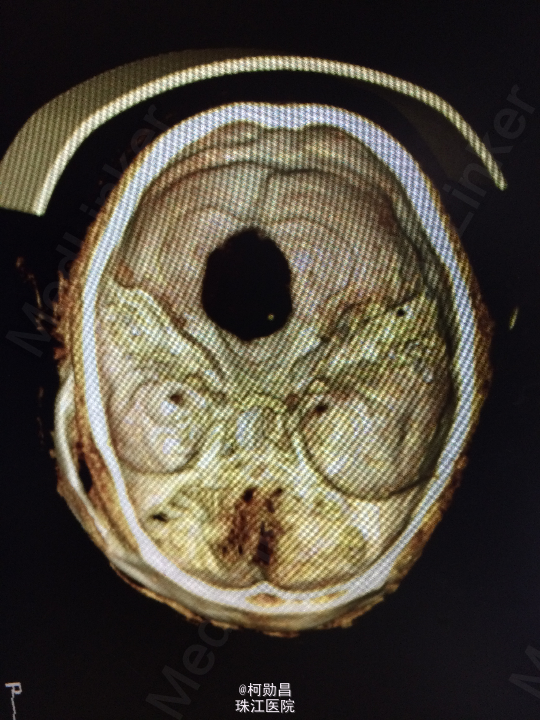

主诉:头痛伴左眼视力下降半年 病史:患者46岁男性,缘于半年前无明显诱因出现头痛,当时未予特殊处理,后症状进行性加重,并发左眼视力下降,于当地医院行头颅CT及MR检查提示颅内占位,为进一步治疗而入我院。 既往病史:5年前曾患鼻咽癌

查体:神志清楚,对答流利,左侧眼裂变小,左侧瞳孔散大,直径4mm,对光反射迟钝,左眼视力下降。右侧正常。 辅助检查:头颅MR提示前颅底筛沟通病变

诊断:鼻咽癌脑转移 处理:全麻下行颅筛沟通占位切除术,术后病理提示:鼻咽非角化鼻咽癌脑转移